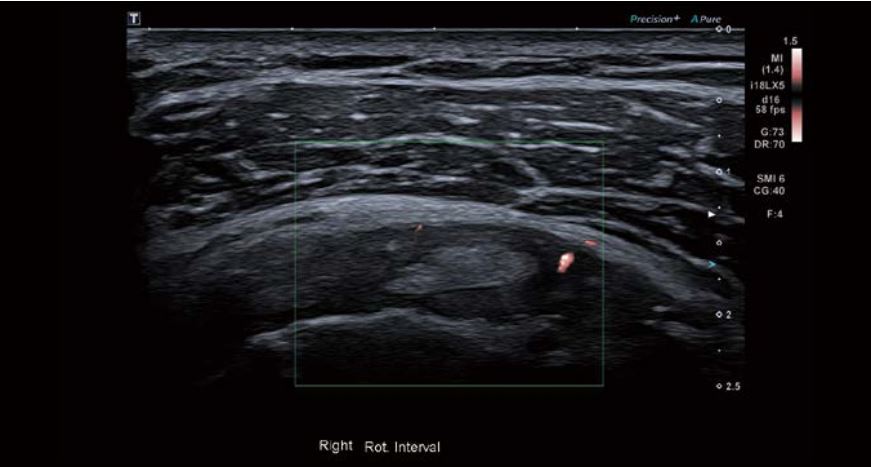

Було виявлено невеликий набряк оболонки сухожилля малого біцепса, потовщення та помірну васкуляризацію проміжку обертальної манжети. Спостерігалося незначне потовщення та асиметрія правої нижньої плечової зв'язки (НПЗ) та підпахвинної западини порівняно з лівою стороною. Товщина суглобової сумки була в межах норми, а в сухожиллях обертальної манжети спостерігалися мінімальні вікові зміни.

Зображення 3 Видно потовщення ділянки обертальної манжети, а режим Superb Micro-vascular Imaging (SMI) демонструє наявність судин